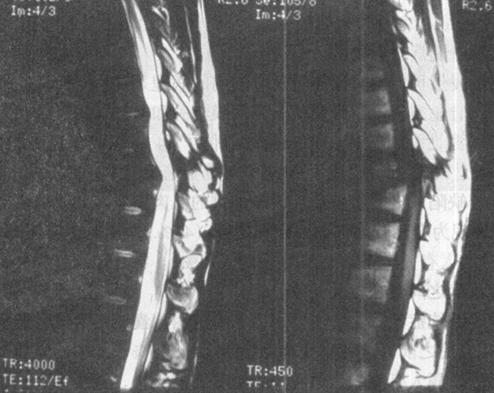

急性脊髓创伤常由于脊柱结构破坏(图7-12a和b),如撕裂伤、横断伤或严重挫伤,也可由内在的可逆性损伤如震荡或轻微挫伤引起,还可以由外来的可逆损伤如脊髓受压引起(图7-13)。按损伤程度分为脊髓震荡伤、脊髓挫伤、脊髓撕裂伤和横断伤。

图7-12a 颈段脊髓横断性损伤。颈椎正侧位片:C5以上前脱位,该水平段椎管狭窄,可推测脊髓受压迫

图7-12b MRI矢状面T1WI可见颈髓在C5水平明显受压,椎体前缘和椎管内可见中等偏高信号,局部颈髓可见斑点状高信号;12WI被压迫的脊髓亦见高信号出血灶,脊椎前方前纵韧带下血肿,呈高信号